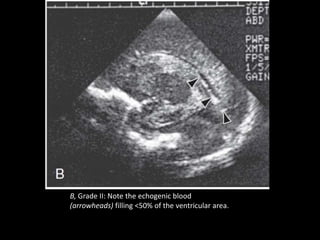

B, Grade II: Note the echogenic blood

(arrowheads) filling <50% of the ventricular area.

B, Grade II:Note the echogenic blood (arrowheads) filling <50% of the ventricular area.